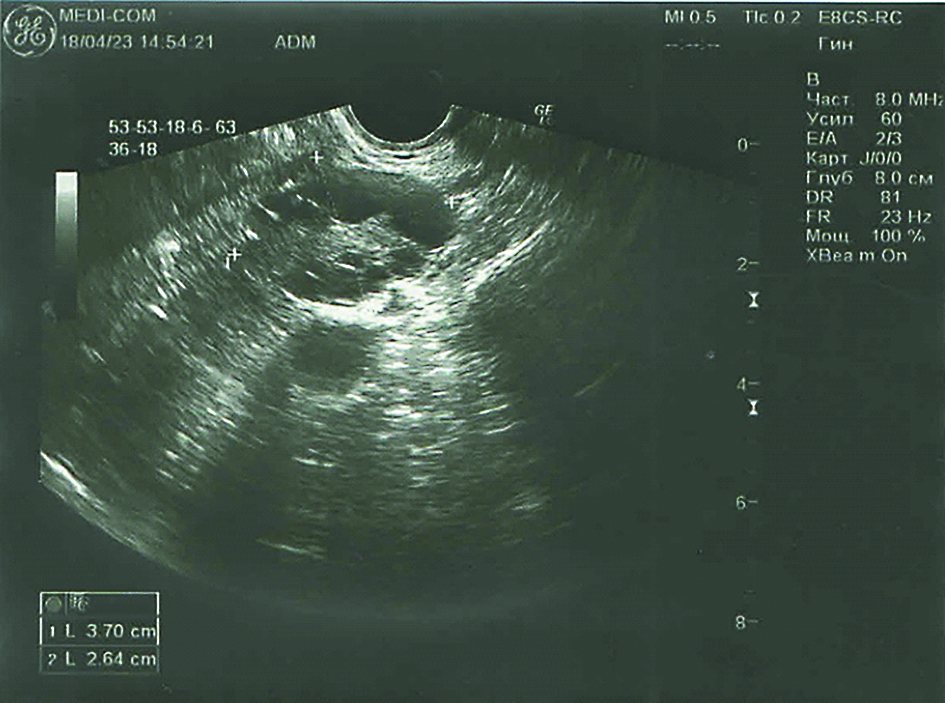

Ультразвуковое исследование осуществляли на аппарате GE Voluson E10 (General Electric) нативно с помощью внутриполостного объемного конвексного датчика RAB2-5-D. Измеряли длину, ширину и передне-задний размер яичников с помощью трансвагинального доступа по стандартным протоколам (рисунок 1).

Рисунок 1. Эхограмма яичника женщины 30 лет.

Figure 1. Echogram of the ovary of a 30-year-old woman.